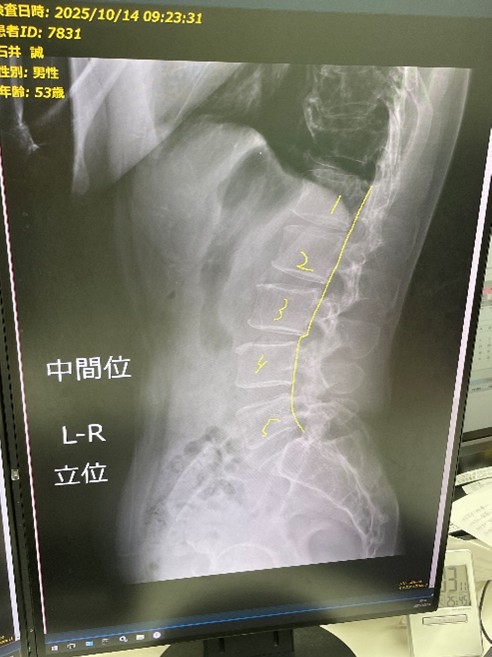

翌日、整形外科を受診。念のためにレントゲンも撮っていただきました。

骨には特に異常はないとのことでした。

(腰椎4番が若干前にずれている程度ですが、この程度なら問題ないとのこと)

という事で診断名は

【筋筋膜性腰痛症・急性腰痛症】(いわゆるぎっくり腰)でした。

骨や神経系に異常があるのではなく、腰部の筋肉・筋膜などに急激に力が加わり、捻挫や肉離れが起きて炎症が起きたとのこと。